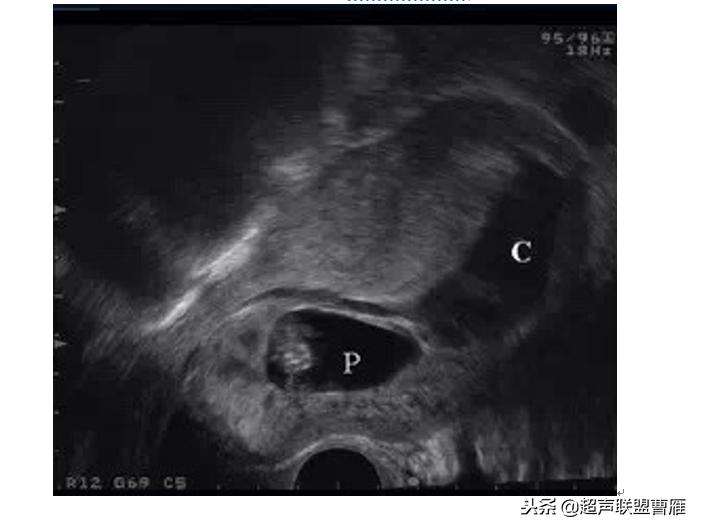

I型胚胎存活型

1.子宫下段见完整妊娠囊,见胎心搏动,见扩张血管及多量血池

2.孕囊周围局部肌层血流信号丰富,可记录到类滋养层周围血流频谱

(I型胚胎存活型)